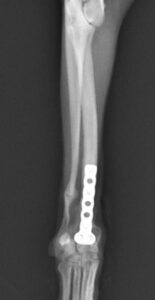

左前腕骨折のトイプードルちゃんの手術がありました。橈尺骨骨折は動物病院では一番よくある骨折です。ロッキングプレートであるTAITANコンディラー1.7mmで対応しました。治りも順調で元気に帰りました。よかったね。